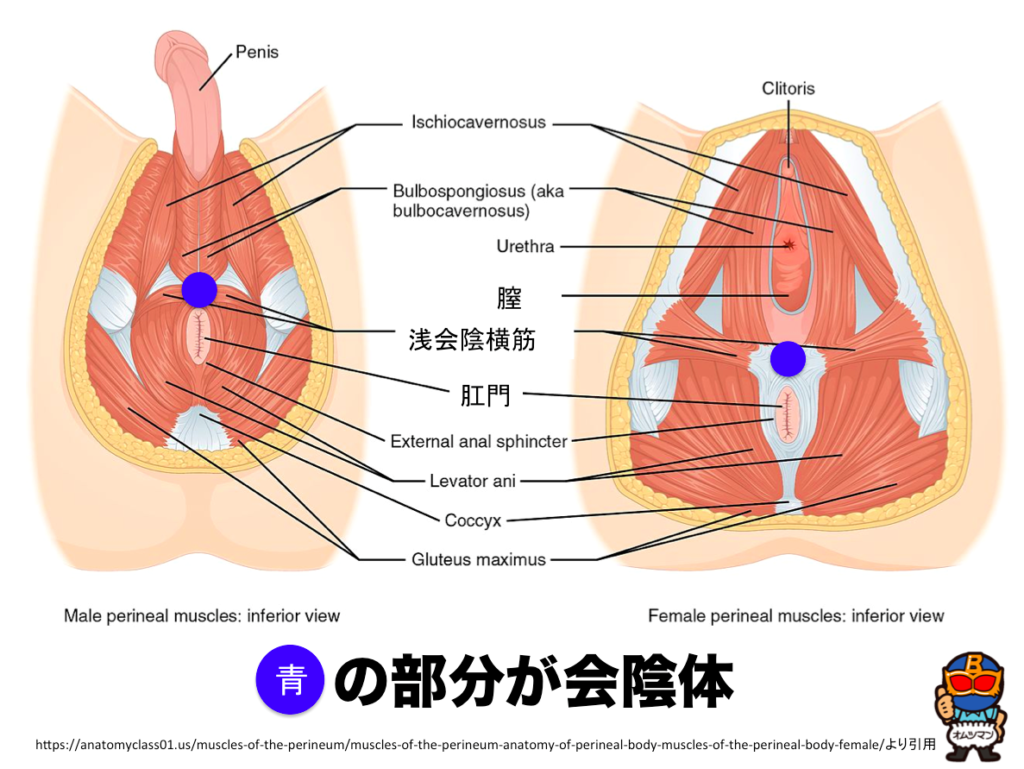

会陰 ( えいん )とは、 解剖学 において、狭義では 外陰部 と 肛門 の間、広義では左右の 大腿 と 臀部 で囲まれる 骨盤 の出口全体をさす。 恥骨結合 と左右の 坐骨結節 、 尾骨 を結ぶ菱形部となる。会陰と残尿感の解消には、 一体どのような関係性があるのでしょうか。 男性は蟻の門渡りを押すことで残尿感を解消できるのか? 排尿を終えた直後なのに「まだ膀胱内に尿が残っているような気がする、 なんだかスッキリしない」という不快感を覚える 男性の陰部のかゆみの原因として考えられる疾患とは? 男性の陰部にかゆみの症状があるとき、大まかな原因としては「性感染症」「皮膚疾患」の2つの場合が考えられます。 かゆみのある性感染症としては「性器ヘルペス・尖圭コンジローマ・梅毒」などがあり、どれも性行為により感染する可能性があります。 性器ヘルペスでは、陰部に水膨れができ

会陰部 広義の会陰の定義 (会陰部も参照) 前方の陰丘、外側の大腿内側面、後方の殿溝と殿間裂の上縁に挟まれた菱形の領域 (M) 狭義の会陰の定義 男性の場合尿道と会陰の間、女性の場合膣と肛門の間を指す (KH237) WordNet the general region between the anus and the男性の会陰は前後径5~6センチメートル、女性では2~3センチメートルである。 この部分の皮膚の正中線には色素に富んだ会陰縫線 (ほうせん)があり、男性では陰嚢縫線に続く。 会陰部皮下には脂肪組織、平滑筋線維が多く存在し、その深部には横紋筋からなる会陰筋層がある。 骨盤腔 (こう)を上方からみると、骨盤下口を会陰筋が筋膜、腱膜 (けんまく)とともに会陰部のヘルニアについて情報をまとめました。 ヘルニア治療辞典 男性と女性では、起こる場所が異なると言われていますが、女性の方がかかる率が高くなっています。 恐らく、女性は妊娠や出産などがあるため、会陰部が大きく収縮することが原因の1つではないかと考えられます。